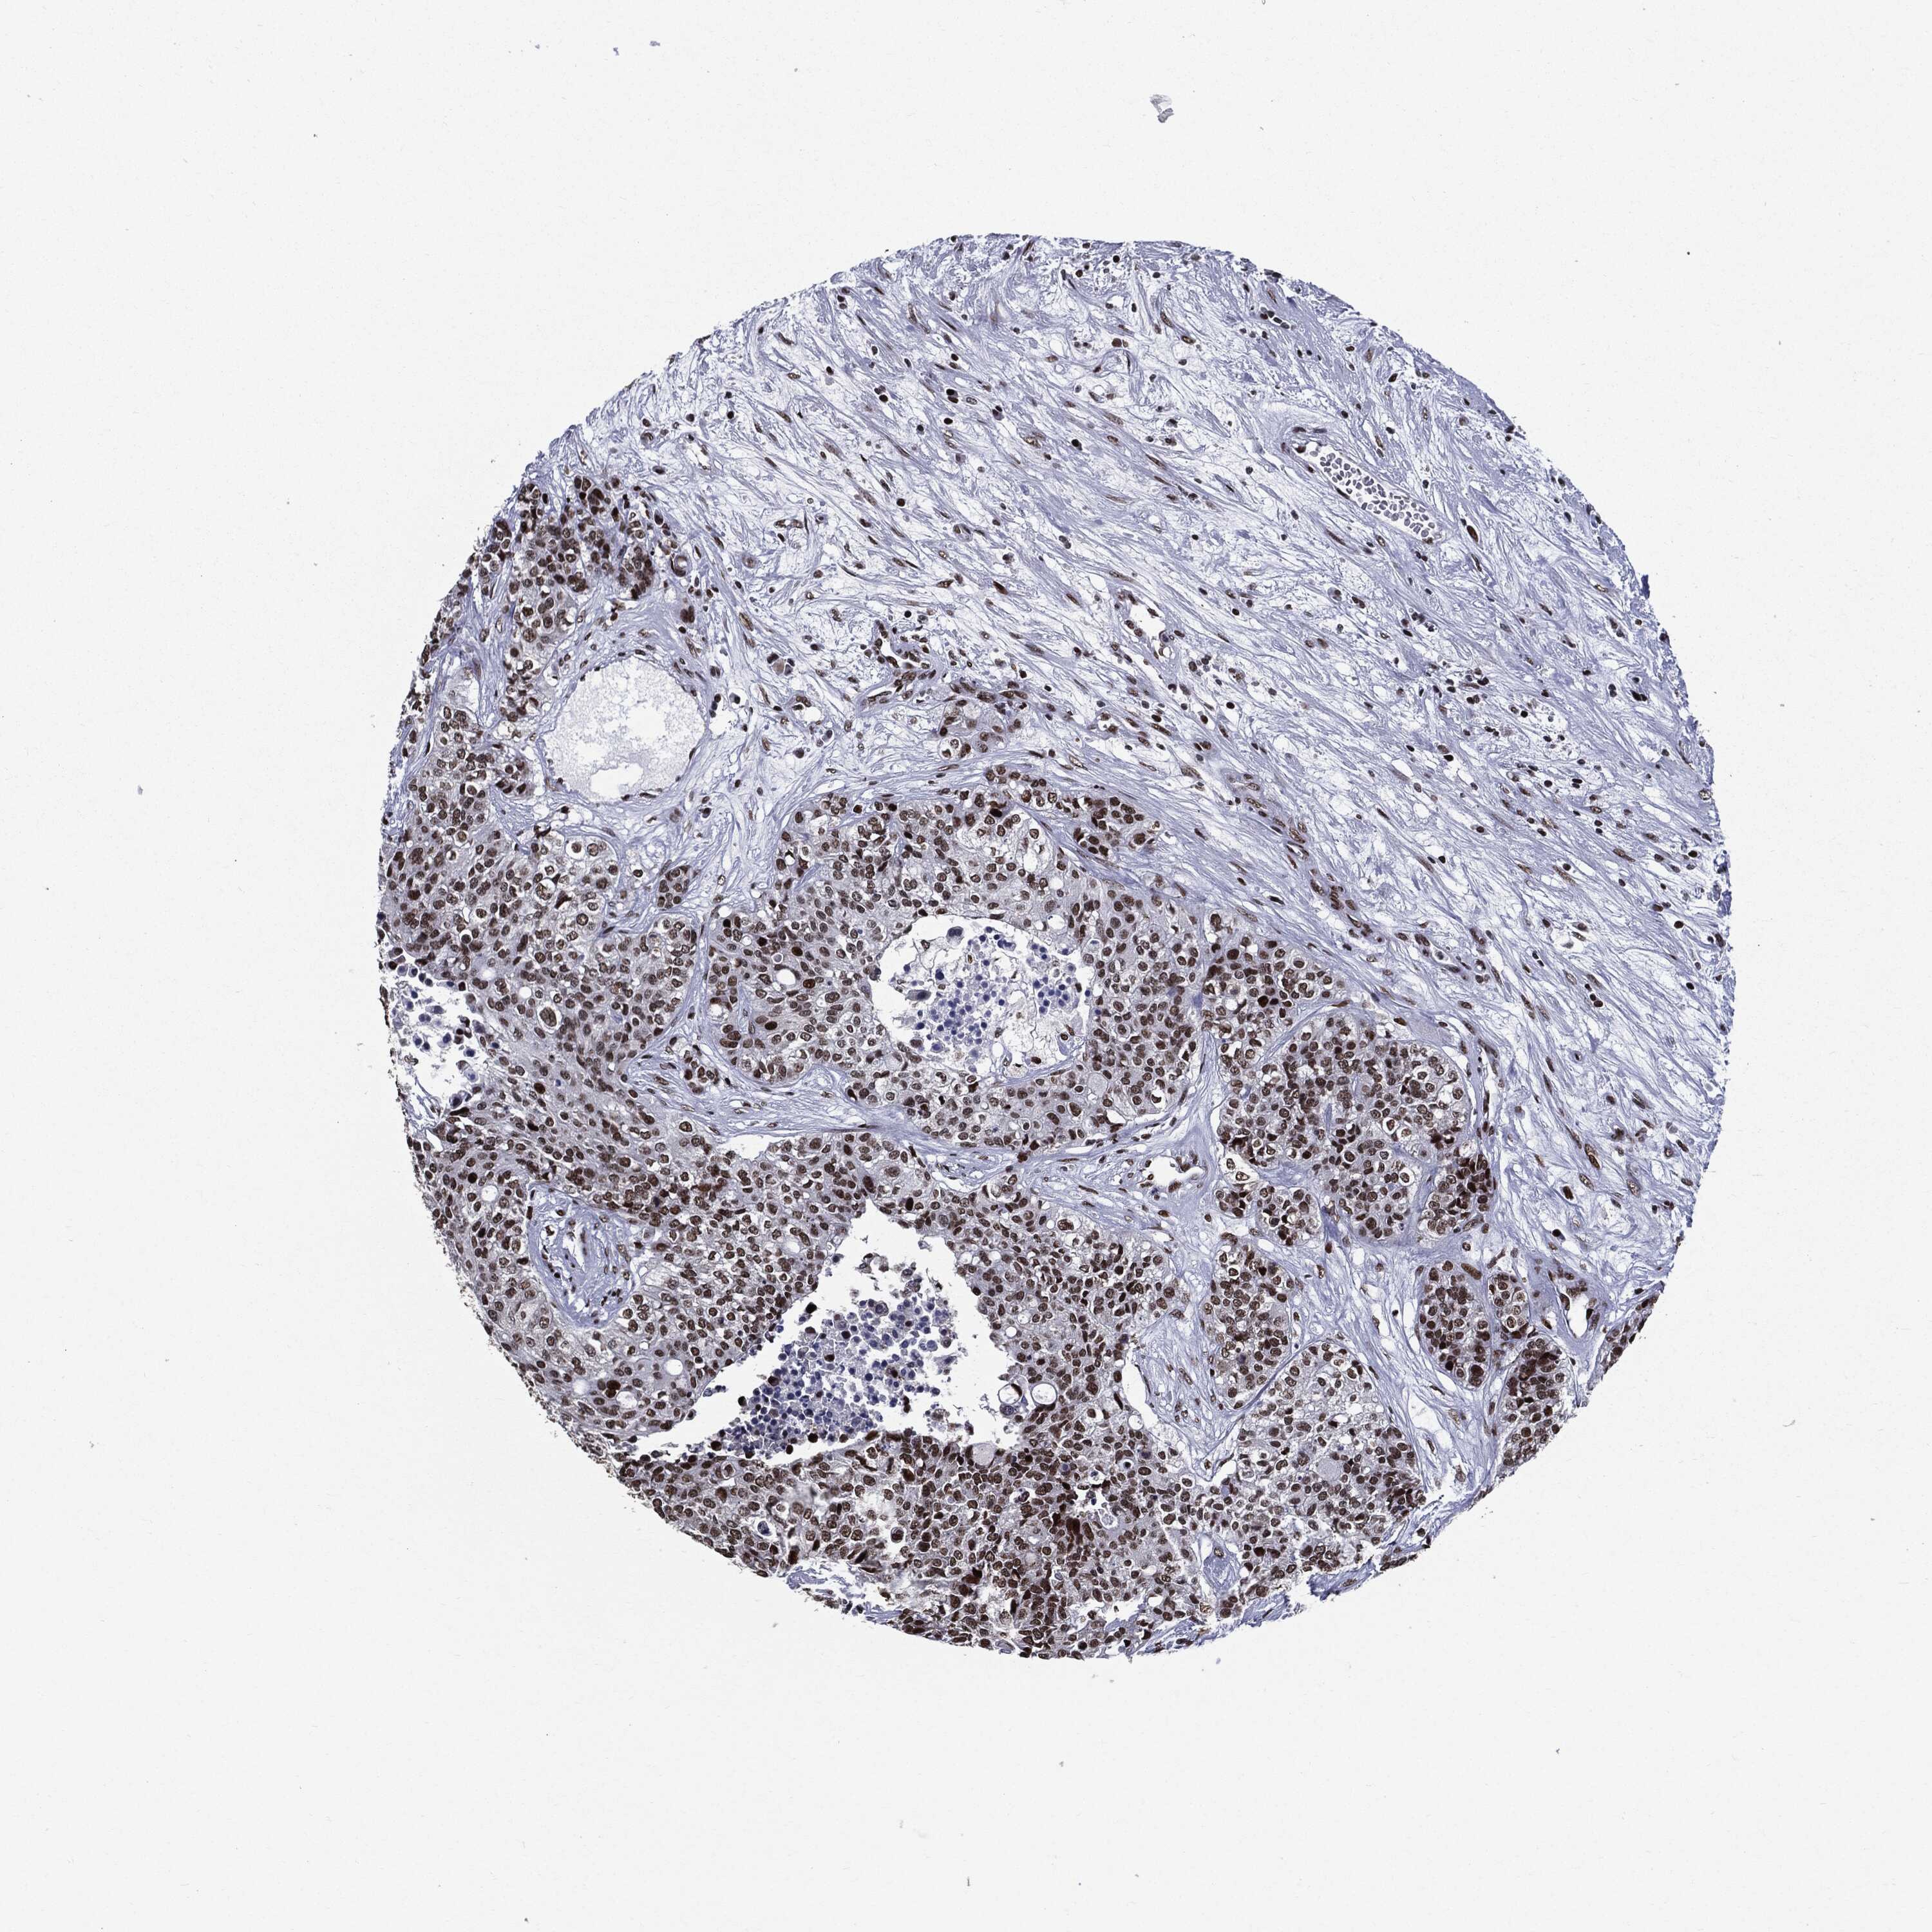

CARCINOID - Protein expressioni

A mouse-over function shows sample information and annotation data. Click on an image to view it in a full screen mode. Samples can be filtered based on level of antibody staining by selecting one or several of the following categories: high, medium, low and not detected. The assay and annotation is described here.

Each image is clickable and will lead to virtual microscopy that enables deeper exploration of all samples and also displays staining intensity scores, fraction scores and subcellular localization as well as patient and tissue information for each sample.

Antibody HPA074591

Staining

Medium

Intensity

Moderate

Quantity

75%-25%

Location

Cytoplasmic/membranous,nuclear

Carcinoid, malignant, NOS